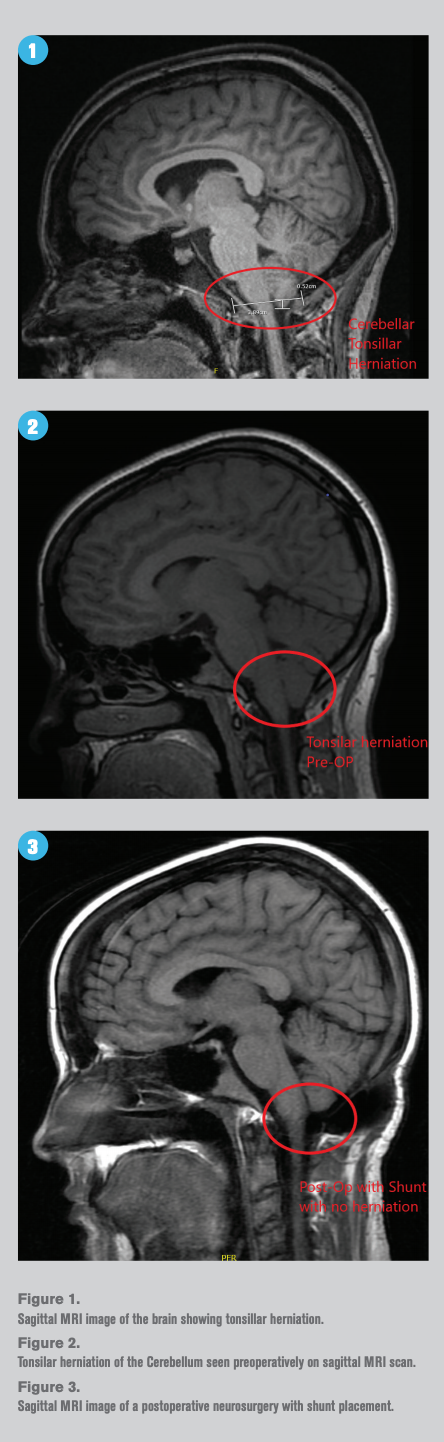

Patients with cerebellar ectopia sometimes have balance problems and may experience symptoms like headaches blurred vision and giddiness. An MRI scan is required to detect malformations of the cerebellar tonsils. Cerebellar tonsillar ectopia includes four types.